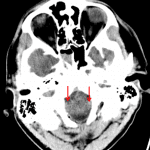

- Acute right cerebral convexity subdural hematoma measuring up to 10 mm in thickness

- Right greater than left cerebral hemispheric sulcal effacement with right to left midline shift measuring 9 mm at the level of the Foramen of Monro, downward transtentorial herniation with effacement of the basal cisterns, and descent of the cerebellar tonsils into the foramen magnum

- Subdural hematoma

- Subarachnoid hemorrhage

- Downward transtentorial and cerebellar tonsillar herniation

Multicompartmental acute hemorrhage including an acute right cerebral convexity subdural hematoma measuring up to 10 mm in thickness and scattered small volume subarachnoid hemorrhage.

Resultant right greater than left cerebral hemispheric sulcal effacement with right to left midline shift measuring 9 mm at the level of the Foramen of Monro, downward transtentorial herniation with effacement of the basal cisterns, and early cerebellar tonsillar herniation.

Mild rounding of the temporal horn of the left lateral ventricle concerning for early ventricular entrapment.